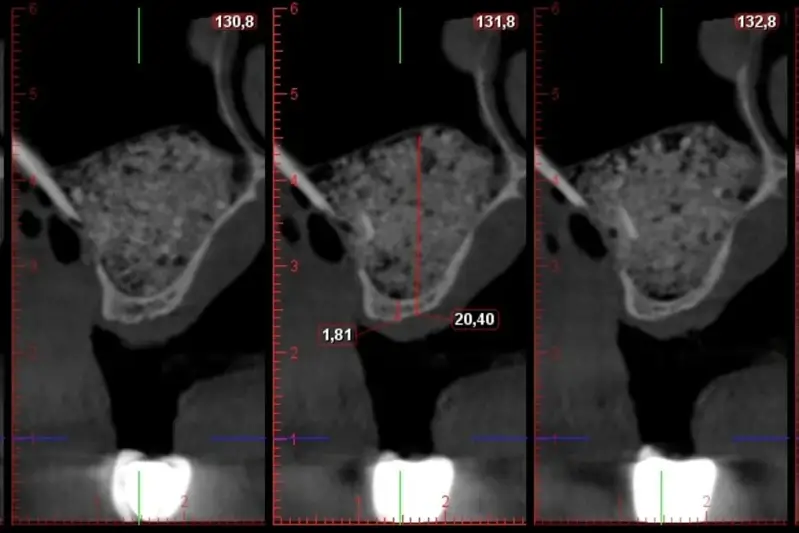

Tras realizar cientos y cientos de Elevaciones con éxito, realizamos esta residencia donde podrás ver desde dentro y ayudar en la cirugía sintiendo el feeling en 1º persona.

Cuando termine la residencia, conocerás nuestro protocolo para tener éxito en el 100% de tus elevaciónes de seno